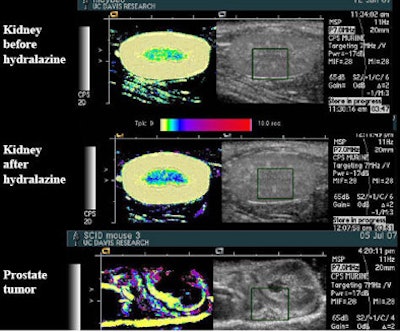

![]() |

| Drugs such as hydralazine and dopamine can be used to perturb the flow of microbubble contrast agents to improve the depiction of perfusion in an organ. The main change seen after administration of the drug hydralazine in the rat kidney, above, was that flow rate slowed, represented by a darker blue in the medulla. Experiments with the flow-perturbing drugs have been shown to be easily reproducible. |

"We can quantify the increase in the amount of time we slow it down by using a drug like dopamine, and if we make multiple measurements of the same region, our standard deviations are small," she said. "These are really good, repeatable studies for this kind of technique." And the ultrasound results can be compared to MRI.